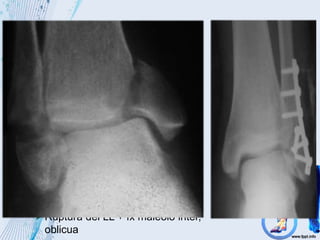

 Mecanismo de producción

Ruptura del ligamento lateral

externo

Avulsión del maléolo externo

Ruptura del LL + fx maléolo inter,

oblicua

Supinación – Aducción

Pronación - Abducción

Ruptura simple del ligamento interno o avulsión

del maléolo lateral y una fx transv del peroné

Fx peronea por arriba del ligamento tibioperoneo

interóseo

Pronación – rotación externa

Quirúrgico

 Indicaciones quirúrgicas

 Fracaso de la reducción cerrada

 Fracturas desplazadas

 Fracturas inestables

Fracturas maleolares internas desplazadas

Fracturas abiertas

Tto especifico